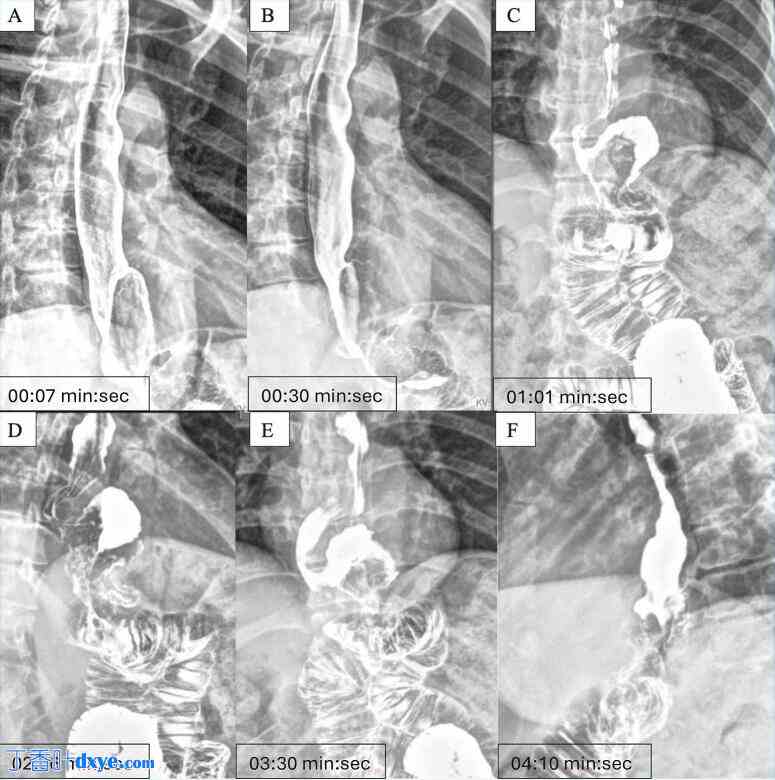

持续存在的症状促使医生进行进一步评估。采用双重对比技术的上消化道造影显示,胃囊较小,造影剂可畅通无阻地流入空肠袢(图1)。然而,观察到活动性胃食管反流,逆行造影剂到达食管中段。上消化道内镜检查显示符合食管炎的炎症改变以及复发性食管裂孔疝的证据。回顾腹部CT扫描报告,排除上消化道梗阻性病变或其他显著的解剖异常(图2)。

OAGB 术前影像

(A) 轴位图像显示 OAGB 特有的 Ω 形机械胃空肠吻合 (*)。

(B) 金属钉勾勒出靠近胆胰袢的胃囊轮廓。这些图像是在转换为 LRYGB 之前获得的。